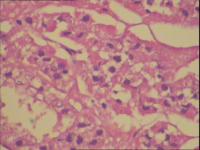

(肾上极)肾细胞癌

性别

男

年龄

50岁

临床诊断

待诊

一般病史

右侧肾上腺肿物,大小3x4cm,边界不清,血供丰富

标本名称

肾上极肿物

大体所见

灰黄组织1块,大小6x3x3cm,部分有包膜,切面灰黄,实性。